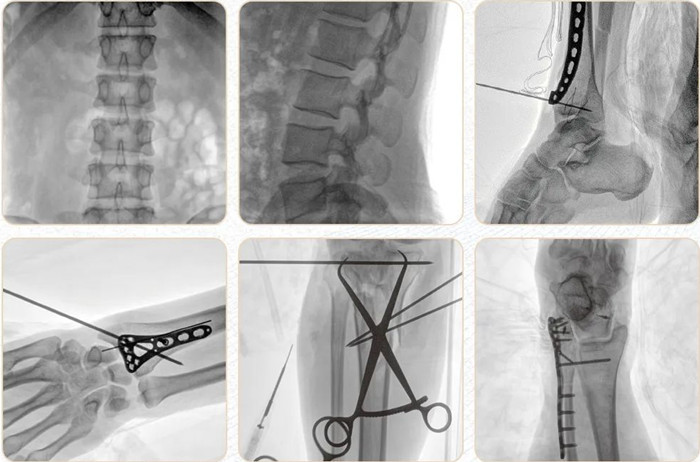

移動(dòng)式平板C形臂PLX118F-Plus臨床應(yīng)用范圍:可應(yīng)用在骨科、普通外科、矯形外科、創(chuàng)傷外科、泌尿外科、脊柱外科、疼痛外科、消化科、腫瘤科、婦產(chǎn)科等科室。